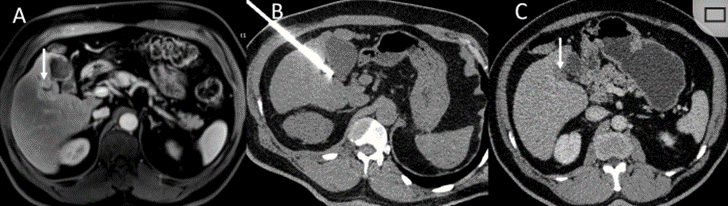

CT引導的冷凍消融

undefined

冷凍消融膽囊附近腫瘤病灶

(A)動脈期 MRI 顯示膽囊附近有外周增強病變(箭頭)。

(B)手術過程中 CT 顯示冷凍探針位于病灶內。

(C)消融后,術后 1 個月CT 顯示完全消融(箭頭)。

冷凍消融肝包膜下肝細胞癌

(A)動脈期CT圖像顯示有一個包膜下結節(jié)(箭頭)。

(B)門靜脈期CT圖像顯示病灶區(qū)(箭頭)。

(C) 在手術過程中的CT顯示一個冷凍探針位于病灶內。

(D)消融后,術后1個月影像CT顯示完全消融。